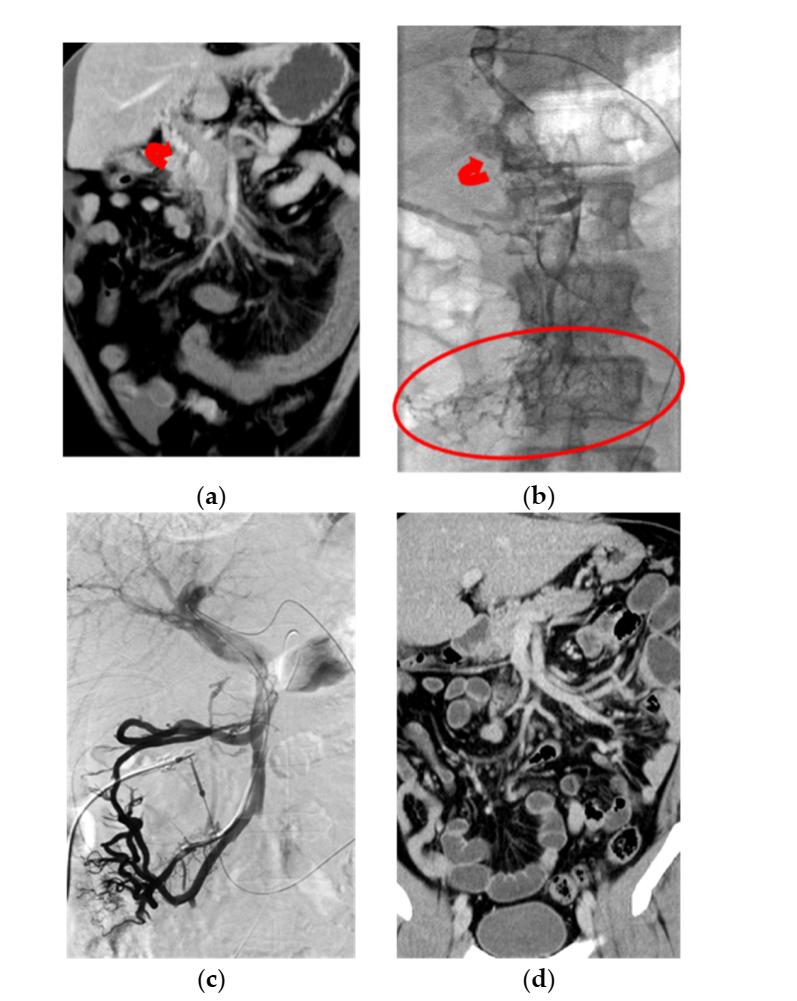

(图源自文献)

一例慢性PMVT急性加重患者,男,40岁,抗凝血酶Ⅲ缺乏症,主诉为腹痛3天。

a

冠状位CT显示:PMV完全闭塞、肠壁水肿增厚、腹水、PV海绵样变(曲线箭头)。

b

经皮肝穿刺PV造影证实CT表现。弥漫性血栓累及肠系膜周围小静脉(圈)和肝内PV。曲线箭头:PV海绵样变。

c

经皮肝穿刺PV造影显示:经肝和SMA途径行局部CDT,于12天输注UK 1160万IU后,SMV、PV主干、肝内PV再通。PV海绵样变未显影。

d

8个月随访冠状位CT显示:PMV通畅,肠袢外观正常。